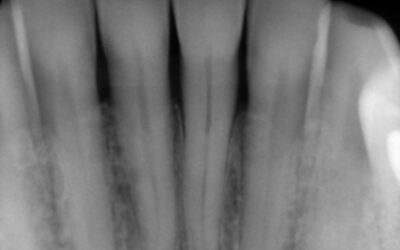

Swollen or receding gum tissue may not seem like a serious issue if you’re about to have your teeth removed or they are already missing. But as gum disease progresses, the severe bone loss that it causes will affect your dental implant options in the future.

Bone loss is a natural effect of gum disease. However, before your dental implant surgery, patients who have weak gum and bone tissues from past periodontal disease may require additional therapies leading up to the implant placement. For instance, if there is extensive bone loss around your lost teeth, a bone graft (augmentation) may be needed to rebuild that area. The grafting process will create a stable environment for your dental implant to set inside.